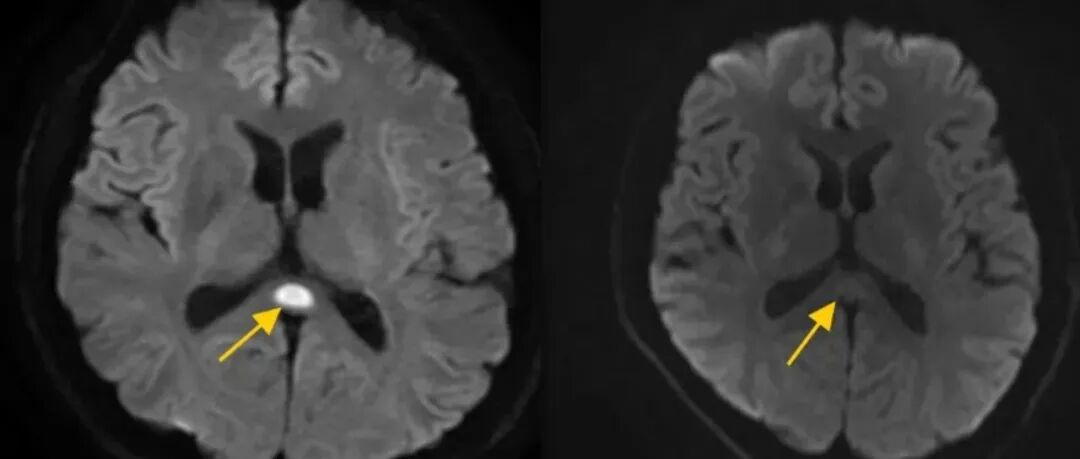

连续半个月这么做,35岁的他被确诊为“脑子坏了”!

一边熬夜、喝酒一边害怕看体检报告说的是不是你?连续15天熬夜喝酒广东深圳35岁设计师董先生(化名)差点“喝坏”脑子持续熬夜喝酒35岁男子确诊为“脑子坏了”小董平时很少喝酒但回老家参加婚礼后一连半个月他